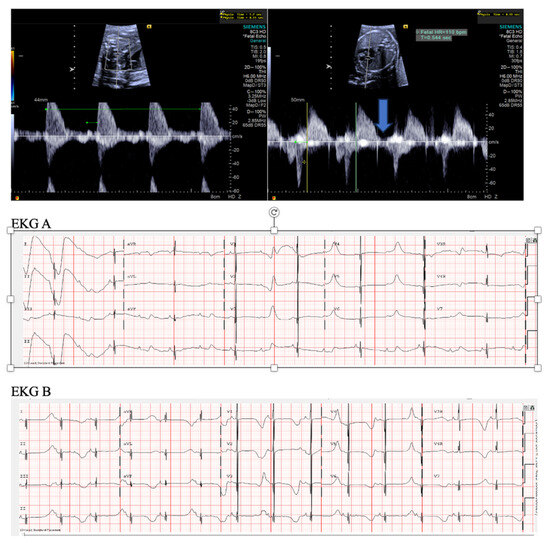

- Short VA SVT (Figure 3 and Figure 4) demonstrates a ventricular–atrial (VA) interval that is less than half of the ventricular–ventricular (VV) interval (VA:AV ratio < 1) and a sudden onset and termination of tachycardia; tachycardia usually terminates with a non-conducted atrial contraction. Short VA SVT includes AVRT (also known as orthodromic reciprocating tachycardia, ORT) and atrioventricular nodal reentrant tachycardia (AVNRT). Short VA SVT typically presents after 18 weeks of gestation.

- Long VA SVT (Figure 4) demonstrates a VA interval that is more than half of the VV interval (VA:AV ratio > 1). Long VA SVT includes EAT and PJRT. A distinguishing feature of EAT is tachycardia termination with ventricular contraction. Long VA SVT may occur as early as 12 weeks of gestation. Because long VA tachycardias have slower rates, they are less likely to cause hydrops.